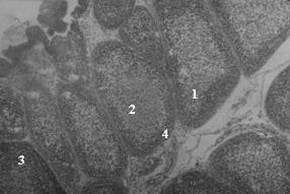

Figura 1: Micrografias de Bursas de Fabricio. 40x. Pollos de 42 días de edad. Grupo A (control) bursa normal, folículos linfoides homogéneos con distribución uniforme de la población linfocitaria. Grupo B (cepa suave), bursa similar a lo observado en el grupo control. Grupo C (cepa intermedia) bursa con aspecto completamente normal, similar a lo observado en los grupos A y B. Grupo D (cepa intermedia plus), se observan folículos linfoides con 1: depleción linfoide centro folicular, 2: persisten aún focos de necrosis, 3: intento de repoblación linfoide, 4: edema interfolicular.

En el estudio de reactividad de las bursa por histopatología (Cuadro 2) se observó que hubo diferencias significativas (P<0,05) a los 8 días post vacunación entre el grupo D (vacunado con la cepa intermedia plus) y el resto de los grupos. A los 16 días post vacunación, la mejor reactividad la presentó el grupo A (control) con diferencias significativas con los demás grupos de tratamiento, mientras que a los 22 días la reactividad fue igual para todos. A los 32 días post vacunación hubo diferencias significativas en el grupo D, presentando menor reactividad (Figura 1) con respecto a los demás grupos.

Giambrone y Clay (1986) indican que las cepas más invasivas y patógenas inducen bursas más pequeñas y mayores lesiones microscópicas en la bursa, por ello el grupo D (cepa intermedia plus) a los 32 días post vacunación presentó atrofia de la bursa y microscópicamente menor reactividad. Estos resultados también pueden ser debido a que la velocidad de recuperación de la bursa varía con la virulencia del virus utilizado (Kim et al., 1999).

Rautenschlein et al. (2003) al evaluar bolsas de Fabricio de aves vacunadas con cepas intermedias observaron recuperación folicular con aumento de la repoblación linfocitaria a los 8 días PV. Rautenschlein et al. (2005) reportan que la cepa intermedia plus, induce lesiones similares con la bursectomia, ya que disminuyen las células de replicación del virus, produciendo incremento de lesiones microscópicas, concordando con los resultados obtenidos.

Los resultados de esta investigación nos indican que en el grupo A (control) y el grupo B (cepa suave) los cambios de maduración folicular son similares y obedecen al progreso orgánico e inmunológico del ave, evolucionando de acuerdo a la edad para la época de beneficio, concordando esto con la relación PB/PC. En el grupo C (cepa intermedia) la recuperación de la población linfocitaria en los folículos linfoides después del proceso de necrosis inicial es adecuada y acorde con la relación PB/PC.

En el grupo D (cepa intermedia plus) la capacidad de los folículos linfoides para reestablecer la población de linfocitos después de los fenómenos de necrosis inducidos por el virus vacunal, fueron insuficientes para la repoblación linfoide adecuada y sólo presentaron reactividad moderada que concuerda con los resultados de la relación PB/PC, recomendándose el uso de este tipo de vacunas en zonas de alto desafío y como segunda dosis.